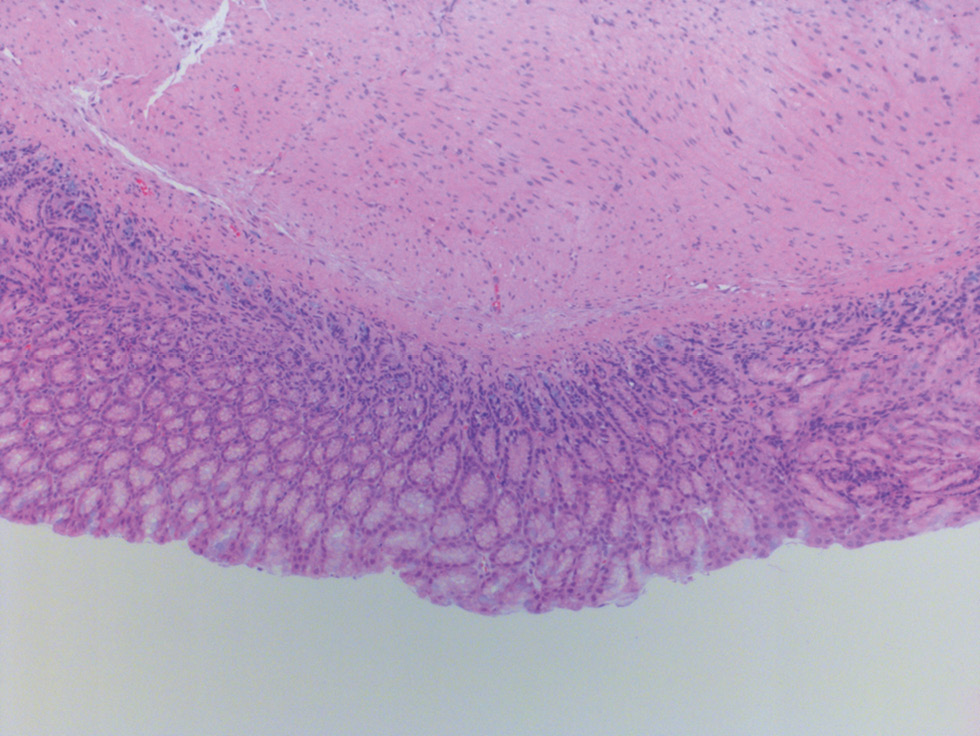

In the morphological study of rats in the control group, we observed high villi in the GMM, shallow dimple-cervical regions, a uniform distribution of glands, and single lymphocytes in the mucous membrane. We also noted that the muscular layer is represented by bundles of smooth muscle fibers, while the serous membrane is covered with a single layer of mesothelium. The thickness of the mucous membrane of the stomach body was 0.50 ± 0.01 mm, while that of the antrum was 0.30 ± 0.03 mm. Histochemical detection of glycosaminoglycans using Alcian blue stain at pH 2.5 in the stomach body revealed focal, poorly expressed production by the epithelium of the superficial parts of the GMM. On the other hand, focal production of glycosaminoglycans in the antrum section was observed in the bottom sections of the glands (Figs. 1, 2).

Fig. 2. Control group rat. Gastric antrum mucosa with focal production of glycosaminoglycans in the area of the glands / Рис. 2. Крыса группы контроля. Слизистая оболочка антрального отдела желудка с очаговой продукцией гликозаминогликанов в области желез

1 In the pictures 1–4 histology slides stained with hematoxylin and eosin with alcian blue additional staining, ×200 magnification.